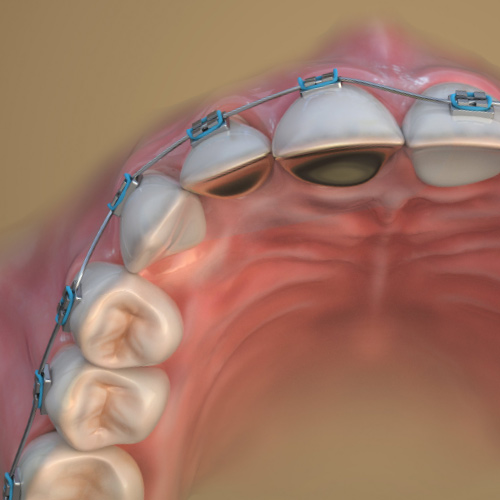

New Directions in Orthodontics

Wednesday, May 8, 2024

This Compendium eBook features a continuing education (CE) article on palatal expansion in skeletally mature adolescents and young adults who have maxillary transverse deficiencies. This eBook also includes an article on the use of clear aligner therapy in tandem with TAD–supported 3D-pri...

Orthodontic Pathways

Tuesday, November 21, 2023

This Compendium eBook features a continuing education (CE) article on guidelines for the orthodontic management of impacted maxillary central incisors. This eBook also includes a case report article on interdisciplinary team management of an esthetic-prosthetic treatment plan for a patient ...

Orthodontic Updates

Thursday, May 11, 2023

This Compendium eBook offers a continuing education (CE) article on recent minimally invasive orthognathic surgical (MIOS) procedures. The authors examine the differences between the minimally invasive and traditional orthognathic surgical techniques, and review the esthetic benefits that c...

Orthodontic Advances

Sunday, December 4, 2022

This Compendium eBook offers two continuing education (CE) articles on orthodontics. The first CE article discusses key aspects of presurgical and postsurgical orthodontics. The second CE article evaluates pre-orthodontic surgical techniques that are utilized to increase bone volume and red...

Breakthroughs In Orthodontics

Friday, December 10, 2021

This Compendium eBook offers a continuing education (CE) article on collaboration between general dentists and orthodontists. Together, through communication and partnership, orthodontists and general dentists can help ensure that the success of the orthodontic treatment lasts for the patie...

Developments in Orthodontics

Tuesday, May 18, 2021

This Compendium eBook opens with a continuing education (CE) article and in-depth case presentation of a complex iatrogenic defect. The accompanying case report explores a treatment plan developed to improve the patient’s lateral profile and lip line, obtain ideal inclination of anterior ...

Advancements in Orthodontics

Monday, November 16, 2020

This Compendium eBook offers a continuing education (CE) article that delves into all aspects of Corticotomy-accelerated orthodontics (CAO). A literature review focuses on an area of increasing concern in pediatric dentistry: early screening for sleep-disordered breathing.

Innovations in Orthodontics

Friday, May 15, 2020

This special Compendium eBook delves into factors affecting malocclusion and bone, beginning with a continuing education (CE) article on surgically facilitated orthodontic treatment (SFOT), followed by an article that features a case report in which a segmental osteotomy was performed.

Spotlight on Orthodontics

Wednesday, December 11, 2019

This special Compendium eBook provides two continuing education (CE) articles that emphasize the importance of teamwork in conjunction with orthodontics.

Today's Trends in Orthodontics

Wednesday, May 8, 2019

This Compendium eBook provides a continuing education (CE) article on fundamentals of interceptive orthodontics. A second article is a clinical review on merging clear aligner therapy with digital smile design.

Advances in Orthodontics

Wednesday, November 21, 2018

Dentistry increasingly consists of many specialties that are brought together in the interest of optimal patient care. This special Compendium eBook contains two continuing education (CE) articles focusing on the role of orthodontics in cases that involve an interdisciplinary team.

Current Topics in Orthodontics

Monday, May 14, 2018

This eBook provides two continuing education articles on orthodontics. The first CE article demonstrates the use of forced eruption and a novel subperiosteal minimally invasive (a)esthetic ridge-augmentation technique, known by the acronym SMART, for the treatment of a complex iatrogenic gingival-al...

Orthodontics

Monday, April 3, 2017

This issue of Compendium's Clinical eBook Series features two continuing education articles aimed at improving orthodontics, including reducing the time needed to complete treatment as well as the use of lasers to enhance esthetic outcomes of orthodontic treatment. Download to earn 4 FREE CEU now!